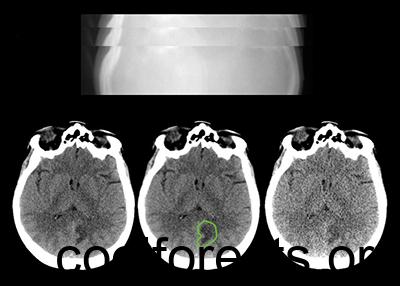

Low Dose CT Imaging and Projection Data. Sample x-ray projection images through a patient’s head (top) are used to reconstruct CT images of the patient’s brain (bottom). Bottom left, a diagnostic quality image is reconstructed using projection data acquired at routine clinical dose levels. Bottom center, the patient’s brain lesion is outlined and corresponding clinical diagnosis data are provided. Bottom right, using a validated noise insertion technique, simulated low-dose projection data are created, which are used to reconstruct intentionally poor-quality CT images. These data will provide a challenge to investigators to develop techniques that create diagnostic quality images from low dose scans, without altering the appearance of pathological lesions. Mayo Clinic photo.

Medical physicists at the Mayo Clinic have just made a unique library of computed tomography (CT) data publicly available so that imaging researchers can study, develop, validate, and optimize algorithms and enhance imaging hardware to produce peak-quality CT images using low radiation doses. In addition to reconstructed images from 300 patient exams, the library includes, for the first time ever, the x-ray projection data used to create cross-sectional images. These data are critical for the development of advanced image reconstruction techniques, including those using artificial intelligence.

“Another unique feature of this library is that we include simulated low-dose data for each patient case,” McCollough said. “Researchers can then use the low-dose data to evaluate the success of their approach in matching or exceeding the quality of the full dose data.”